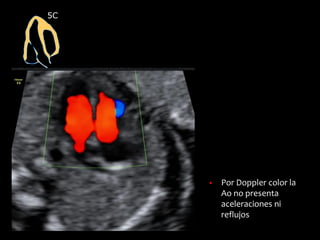

5C

▪ Por Doppler color la

Ao no presenta

aceleraciones ni

reflujos